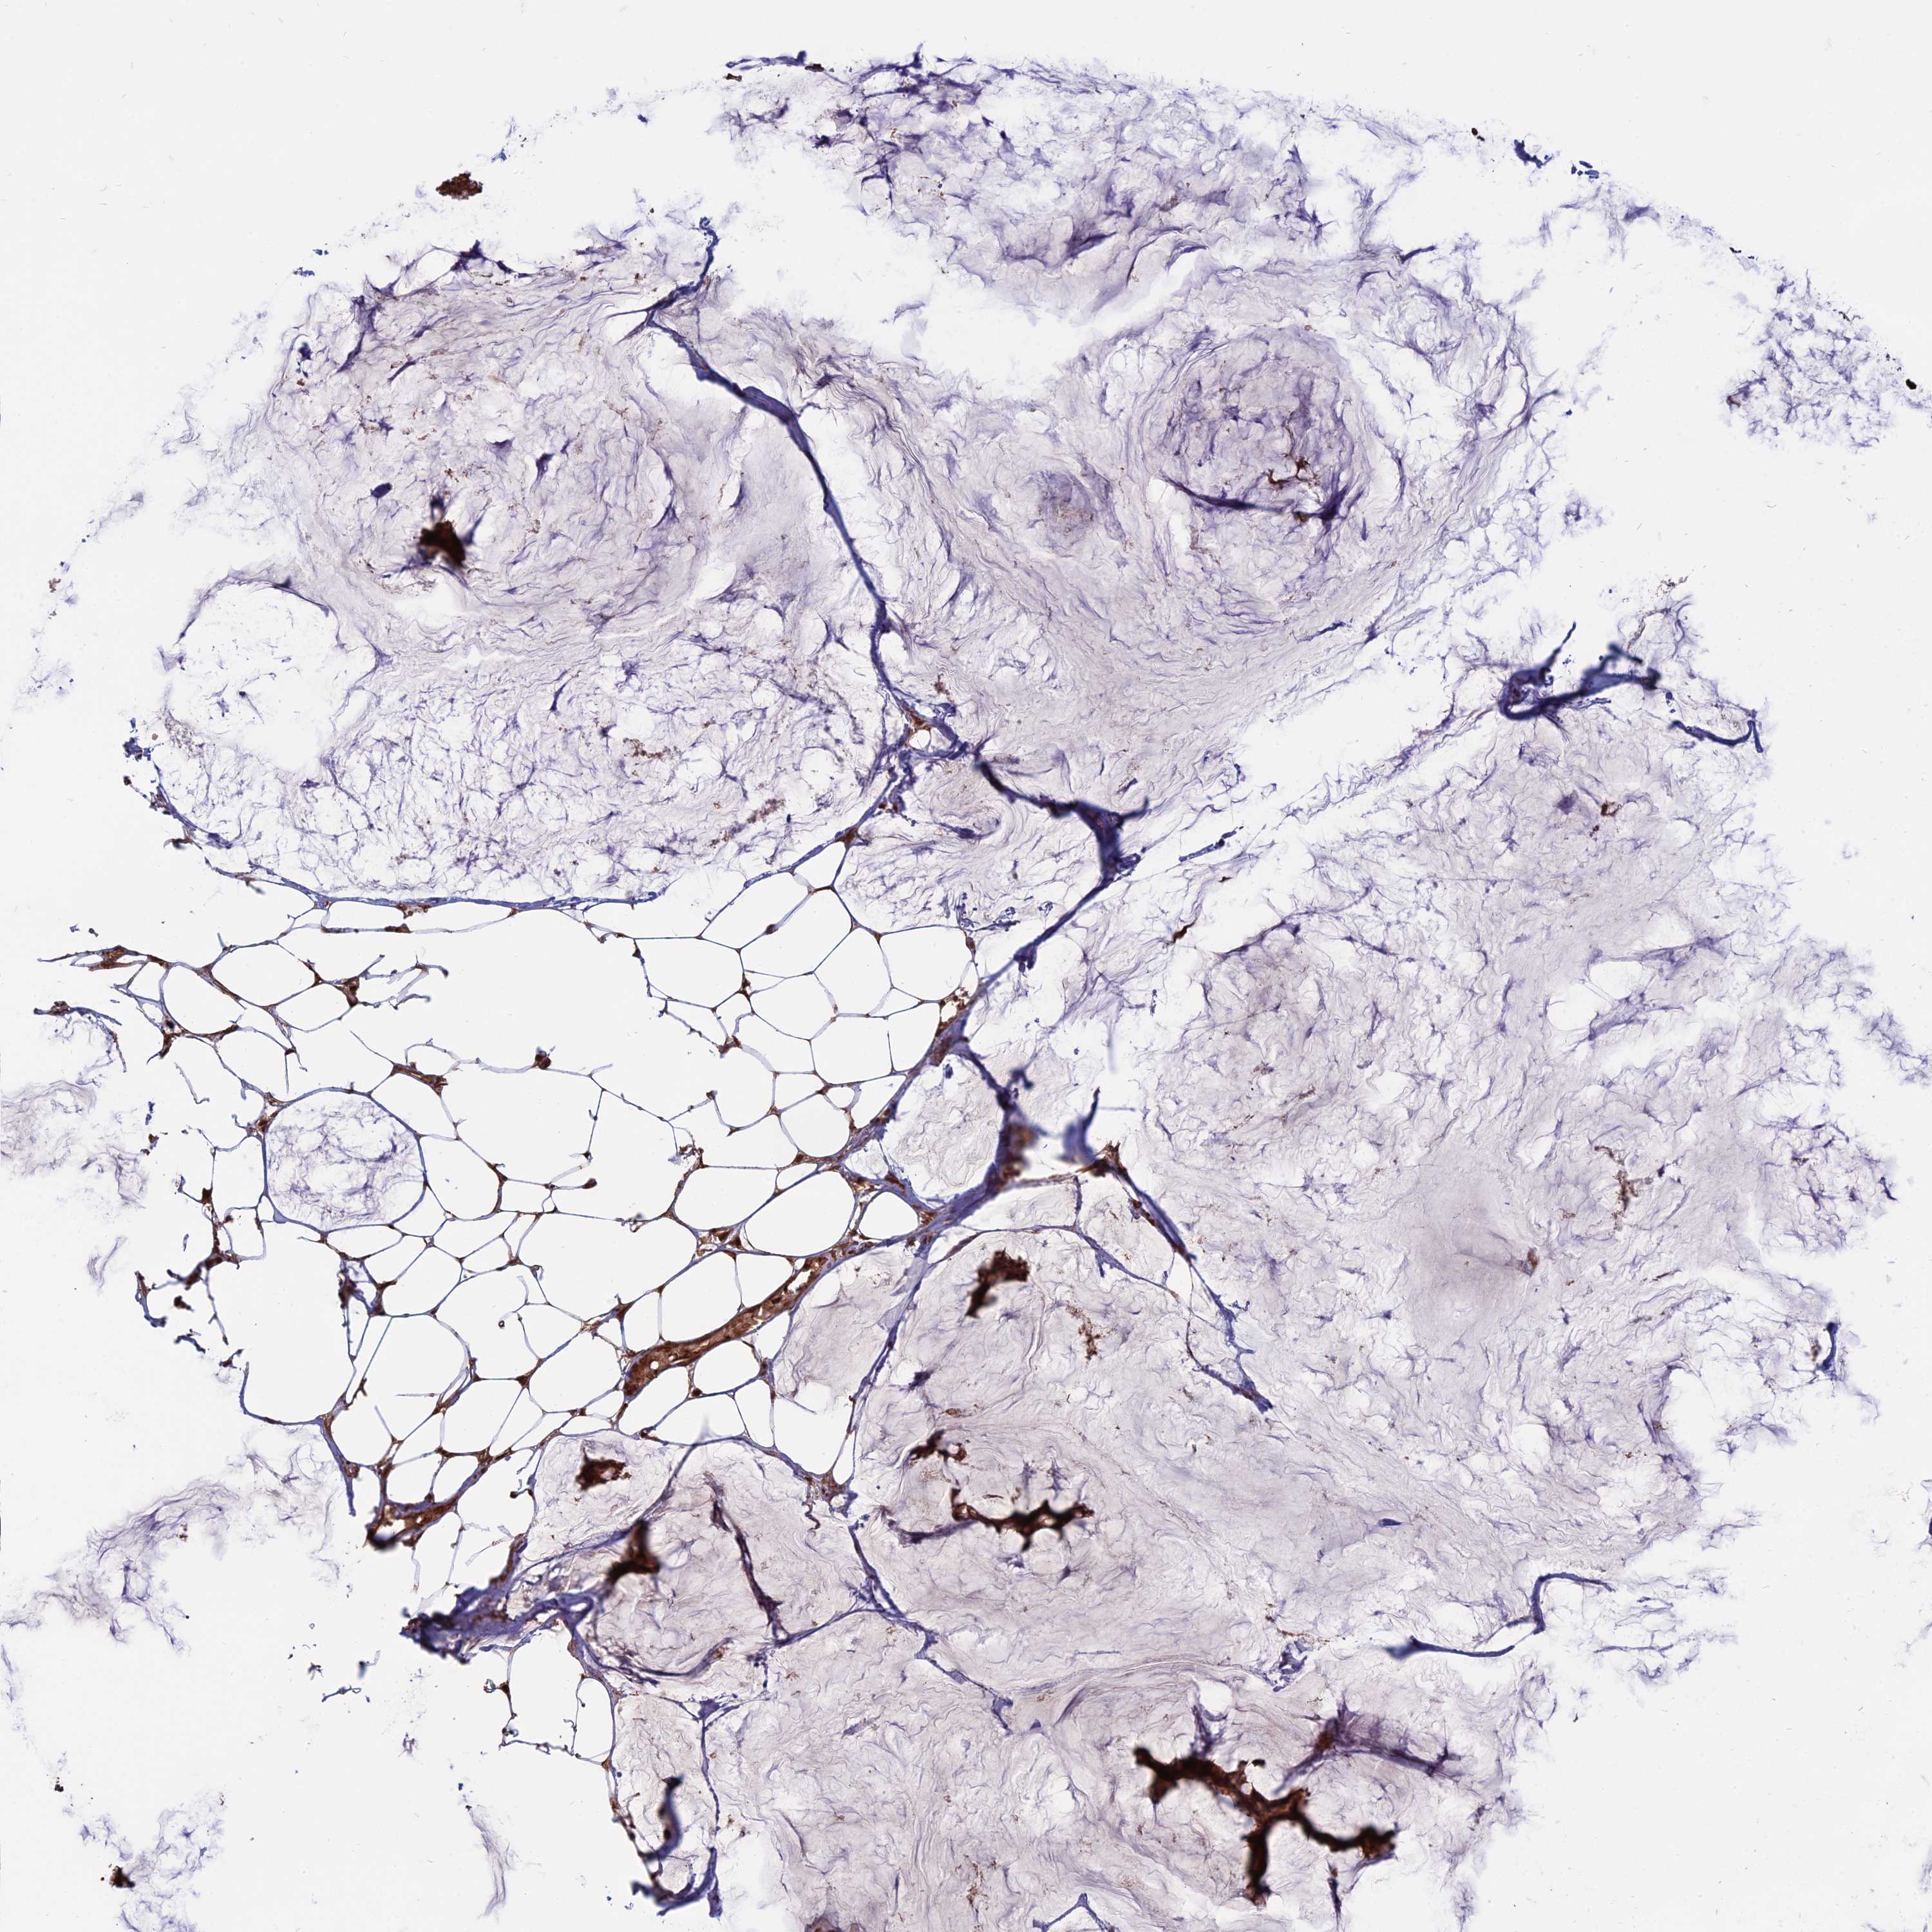

BRCA TCGA BRCA VALIDATION PROTEIN EXPRESSION

ANTIBODIES

AND

VALIDATION